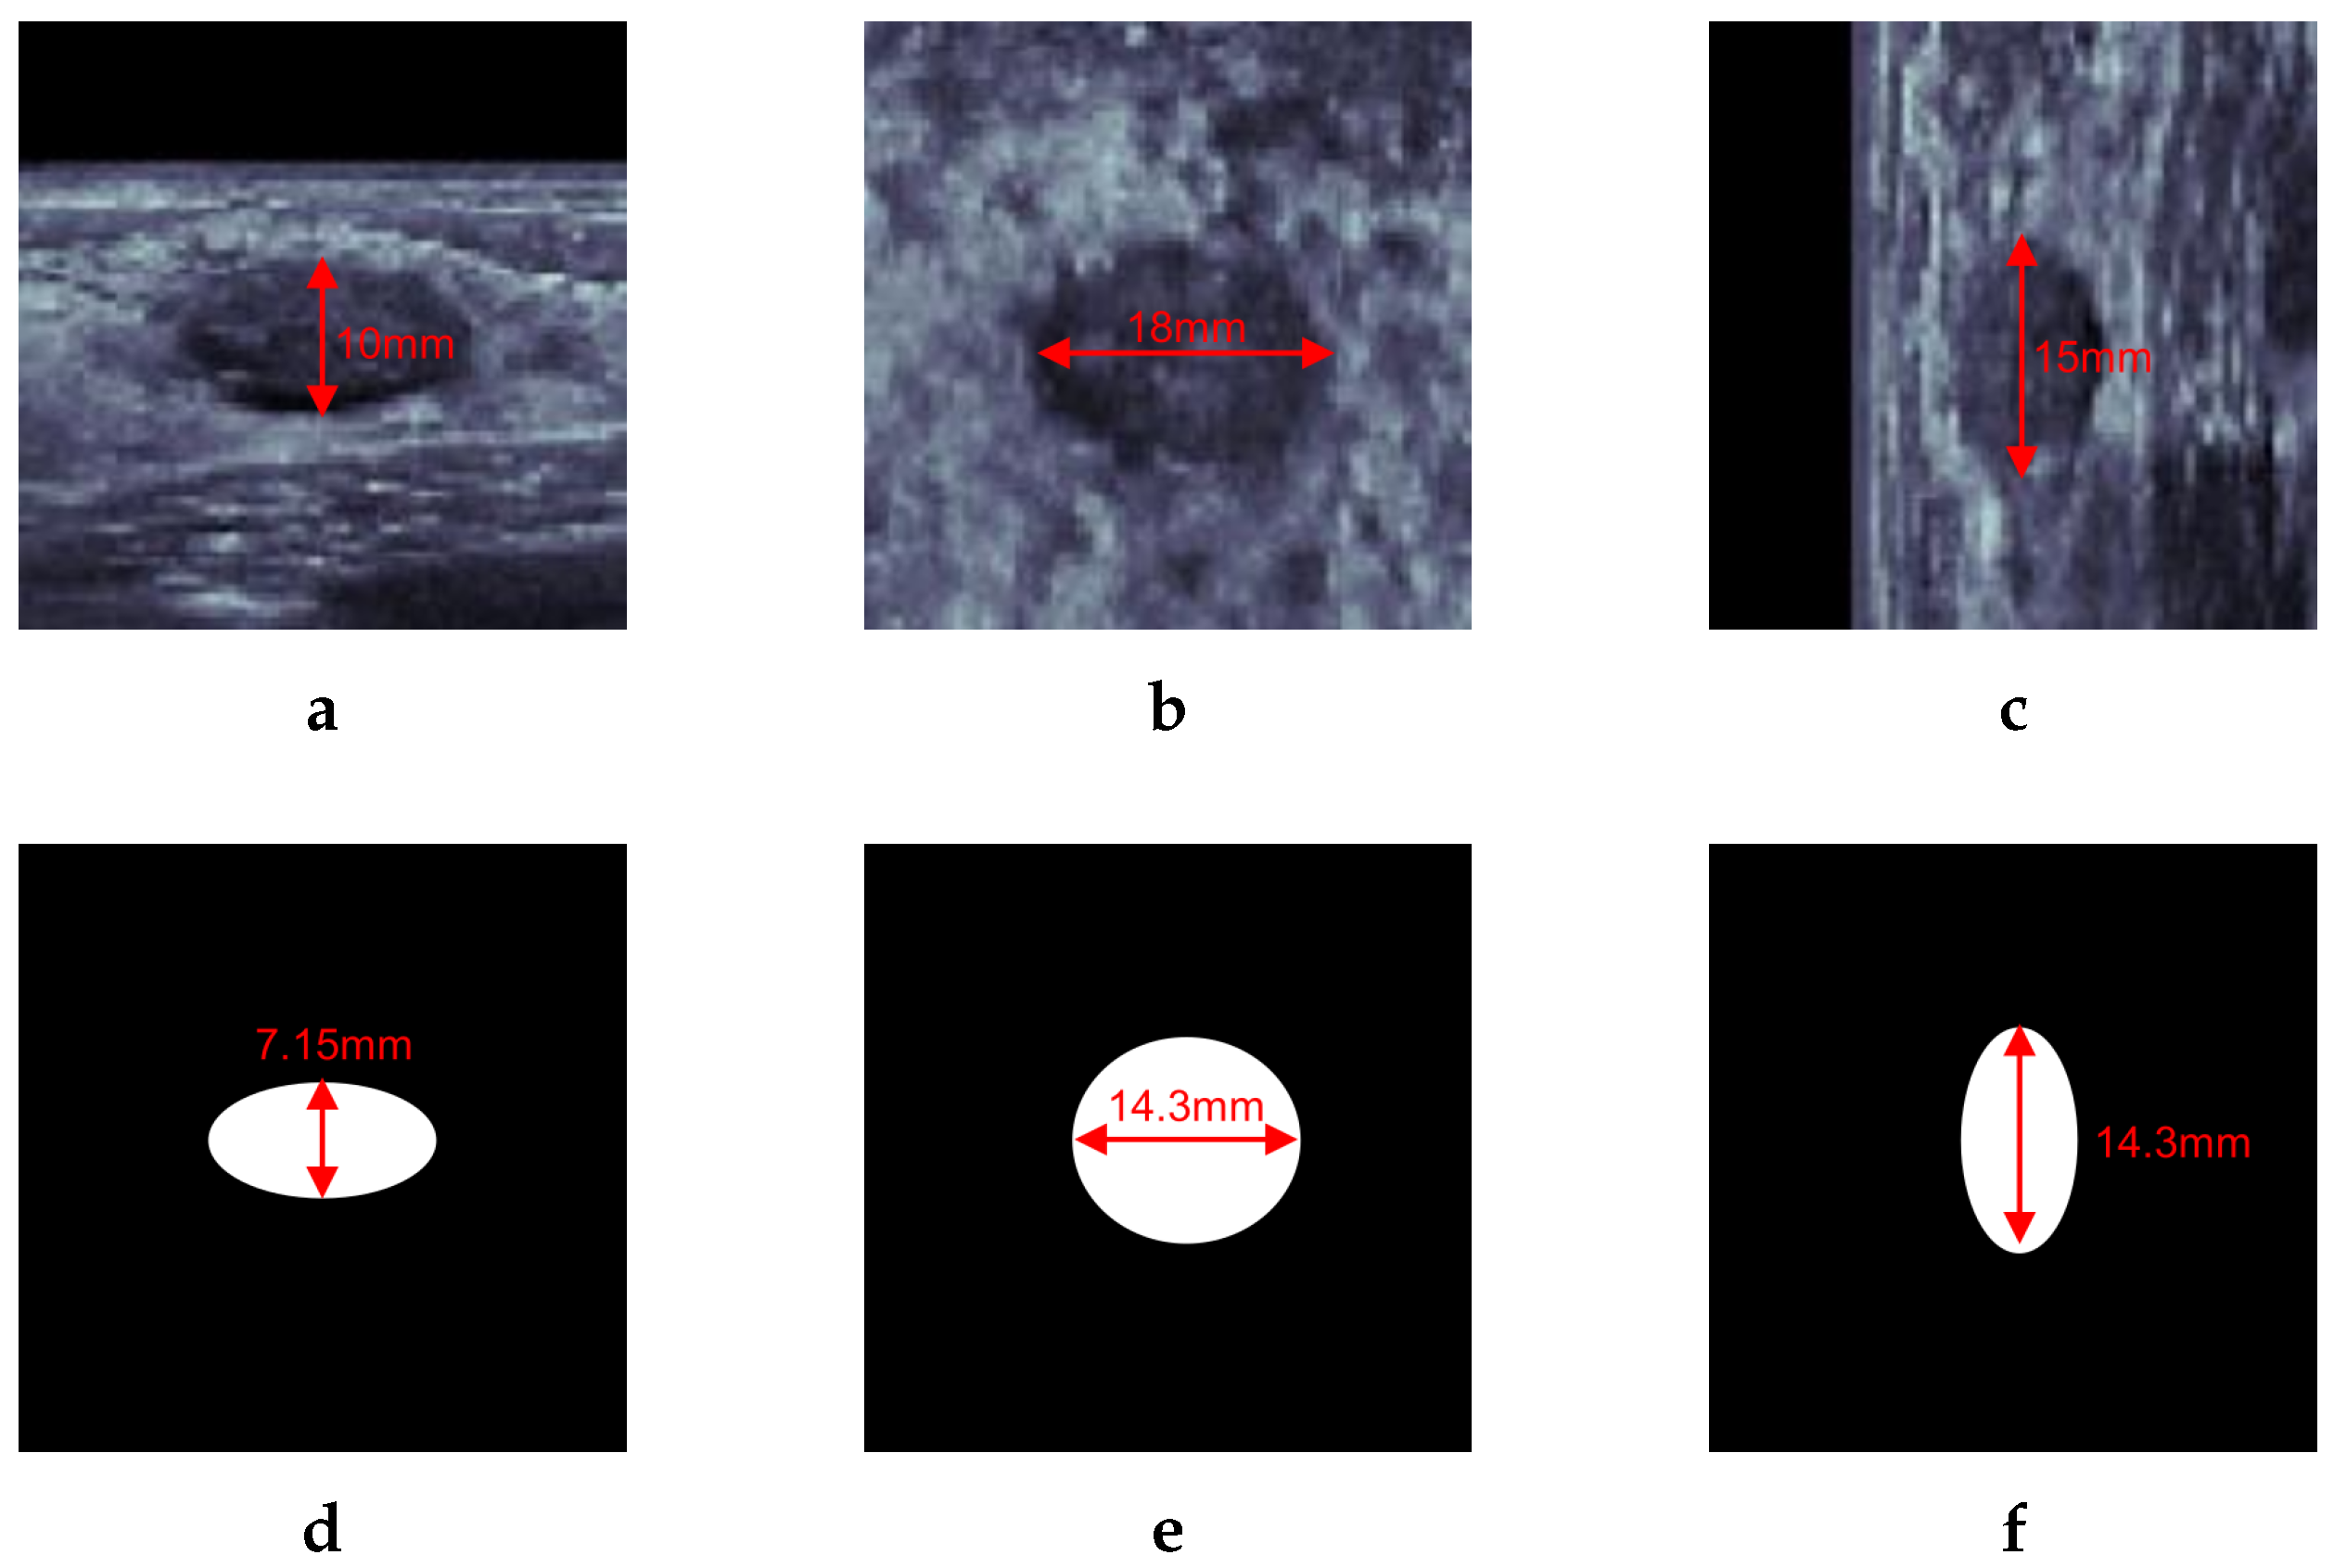

An example of a template mask is shown in Figure 4 with a sampled breast cancer. Figure 4a–c show transverse, coronal, and sagittal views of the center of a breast lesion. With lesion diameters of 10 mm, 18 mm, and 15 mm on each axis, the average diameter was 14.3 mm. The centroid of the template mask is located in the same position as the center of the lesion. Since the lesion has a ‘parallel’ feature of orientation, the positive area shrinks in the skin-perpendicular direction, obtaining the shape of an ellipsoid whose semidiameters are one of 7.15 mm and two of 14.3 mm, as shown in Figure 4d–f.

Figure 4.

Example of template mask. (a–c) Slice image of transverse, coronal, sagittal view of breast cancer on ABUS including diameters of each axis. (d–f) template mask matched to (a–c). Using average diameter of the lesion, the mask label has two of equal semidiameters of 14.3 mm and 7.15 mm semidiameters, which is the half-length of the other diameters due to parallel orientation property.